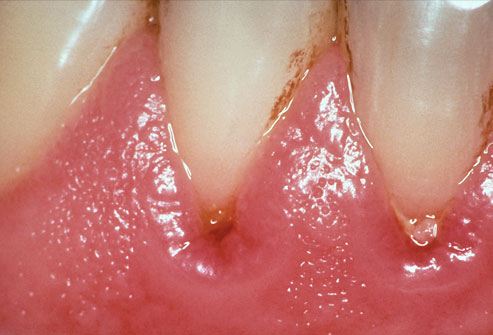

K05 Гингивит и болезни пародонта

Гингивит - воспаление десны.